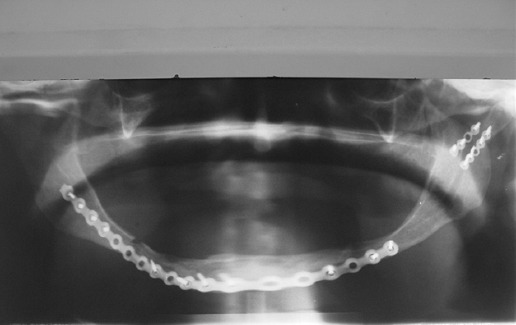

Los sistemas bloqueados con tornillos 2.4 se aplicaron por vía extraoral. Las osteosíntesis fueron colocadas con tres o cuatro tornillos a cada lado de la fractura (Fig. 7); en los casos con fracturas bilaterales con una sola placa, se colocaron el mismo número de tornillos en ambos ángulos-rama y otros tantos en el mentón (Fig. 8).

Figura 8 Fractura bilateral de cuerpo mandibular tratada con una sola placa cerrojada, con cuatro tornillos en cada extremo y dos tornillos en la zona anterior mandibular.

En caso de presentarse este tipo de fracturas, la evidencia muestra que su pronóstico es mejor cuando reciben tratamiento quirúrgico mediante reducción abierta y osteosíntesis con placas y tornillos, en comparación con tratamientos cerrados o alambrados. De las diversas técnicas de osteosíntesis, consideramos que la opción que brinda mayor posibilidad de una buena consolidación la constituyen los sistemas bloqueados, incluso con perfiles de 2 a 2.5 mm de grosor y con tornillos de 2 mm de diámetro. Es conveniente utilizar placas largas, que se coloquen con un efecto de puenteo sobre el cuerpo mandibular, considerando que es el sitio más frecuente de fractura en la mandíbula atrófica, anclando cuatro tornillos en cada extremo, es decir, ángulo-rama y sínfisis-parasínfisis, que son las dos áreas de la mandíbula que conservan mejor calidad ósea. En caso de fracturas bilaterales de cuerpo, la osteosíntesis debe ser realizada con una sola placa que abarque ambos ángulos y la zona del mentón, para que de esta forma se tenga una estabilidad mecánica suficiente para favorecer el proceso de consolidación; no sobra decir que los tornillos deben estar colocados en las zona ángulo-rama y otros en el mentón, idealmente en número de cuatro o por lo menos tres en cada segmento.